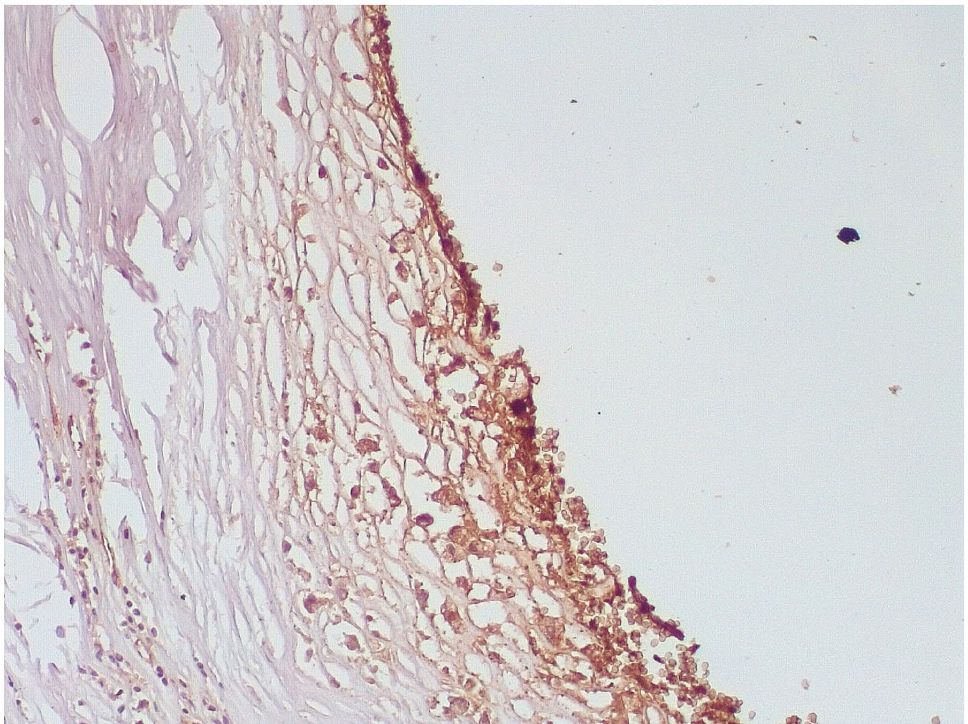

Обращало внимание, что в местах «оголенного» эндотелия КА отмечалась слабая экспрессия белка CD31, что указывало на выраженные дистрофические и некробиотические изменения клеток (рис. 2). При этом экспрессия ФВ была яркой, выраженной на всем протяжении интимы КА (рис. 3).

Сохранялась резковыраженная яркая экспрессия ФВ как со стороны интимы, так и субинтимально, в участках альтерации атером (рис. 8). В то же время экспрессия белка CD31 была негативной на всем протяжении стенок КА.

Наиболее значимым маркером эндотелиальной дисфункции, отражающим нарушение коагуляционных свойств крови, является белок фактор Виллебранда, экспрессия которого была резко выраженной во всех группах умерших после стентирования КА.